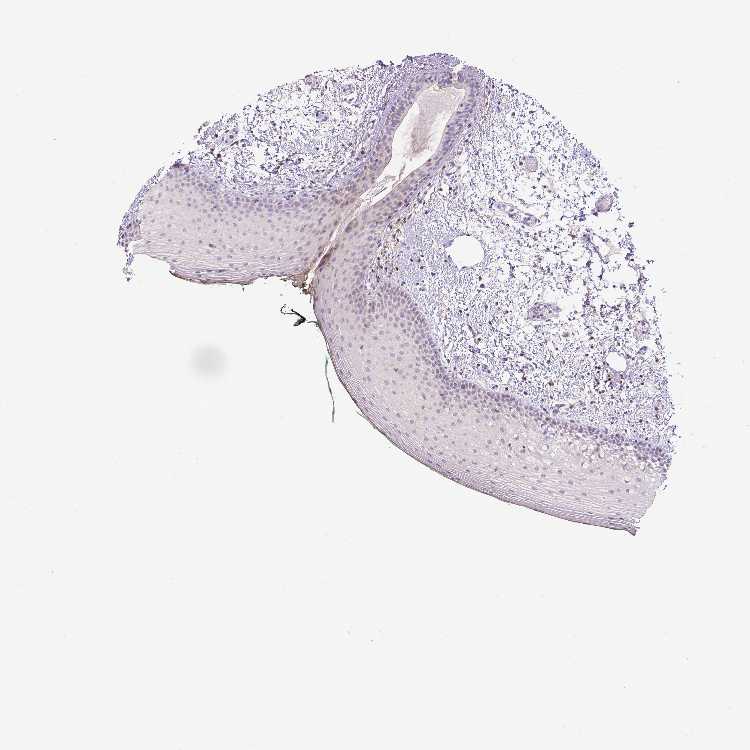

TISSUE PRIMARY DATA ORAL MUCOSA Show tissue menu

ORAL MUCOSA - Antibody stainingi

Antibody staining in the annotated cell types in the current human tissue is reported as not detected, low, medium, or high, based on conventional immunohistochemistry profiling in selected tissues. This score is based on the combination of the staining intensity and fraction of stained cells.

Each image is clickable and will lead to virtual microscopy that enables deeper exploration of all samples and also displays staining intensity scores, fraction scores and subcellular localization as well as patient and tissue information for each sample.

Antibody HPA004252Antibody HPA004472Antibody CAB000011Antibody CAB068180

Squamous epithelial cells LowNot detectedNot detectedNot detected